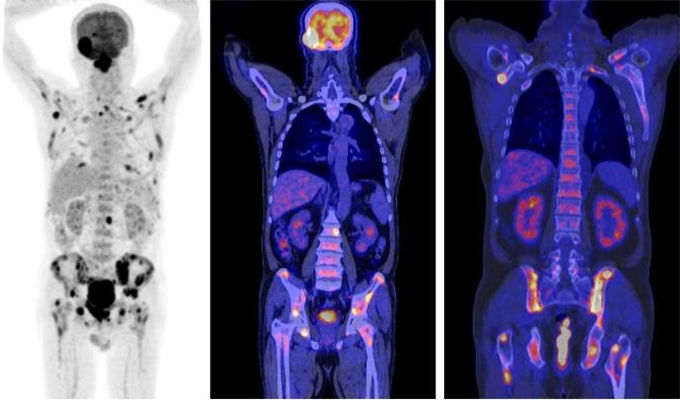

PET/CT

This is a new advanced imaging tool that combines the modalities of CT (computed tomography) and PET (positron emission tomography) in one imaging procedure. The PET scan detects the metabolic signal of actively growing cancer cells in the body whilst the CT scan provides a detailed picture of the internal anatomy that shows the location, size and shape of cancerous growth. The results of PET/CT scans are digitally fused together providing complete information on cancer location and abnormal cellular metabolism. PET/CT combines the high sensitivity of PET with the high anatomical spatial resolution of multislice CT. This integrated approach of PET and CT technologies into a single imaging procedure permits accurate tumour detection and anatomical localisation for many cancerous growths.